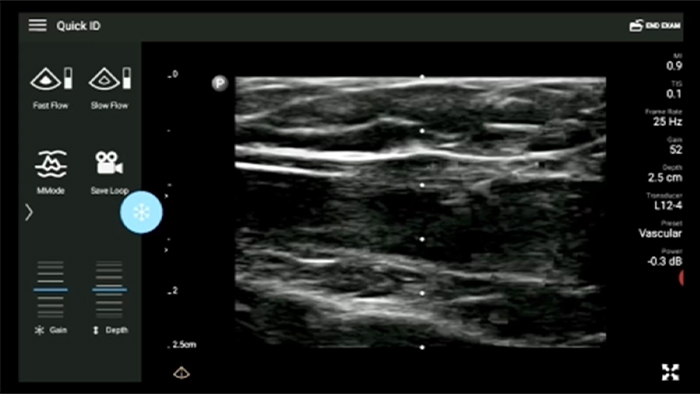

Exceptional ultrasound imaging

Lumify handheld ultrasound offers images that enhance diagnostic confidence.

See more when it counts

Lumify can help you make real-time decisions with more confidence, from assessment to recovery. Reveal the subtle details of an image, uncover enriched tissue definition with multiple angles and much more.